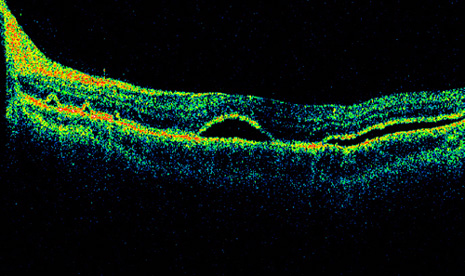

A helpful intraoperative sign to determine the adequacy of subretinal fluid drainage is to assess the contour of the retina in relation to the scleral buckle. If after drainage the retina follows the contour of the buckle, drainage is usually adequate even if there are residual subretinal fluid and retinal folds. However, if after drainage and elevation of the buckle the retina does not appear to follow the contour of the buckle or if the buckling effect is not visible beneath the retina, additional drainage usually is necessary (Fig. 33).

Fig. 33. A. Retinal tear elevated after drainage and placement of a scleral buckle. B. Retinal tear partially closed after drainage with the retina conforming to the shape of the buckle.